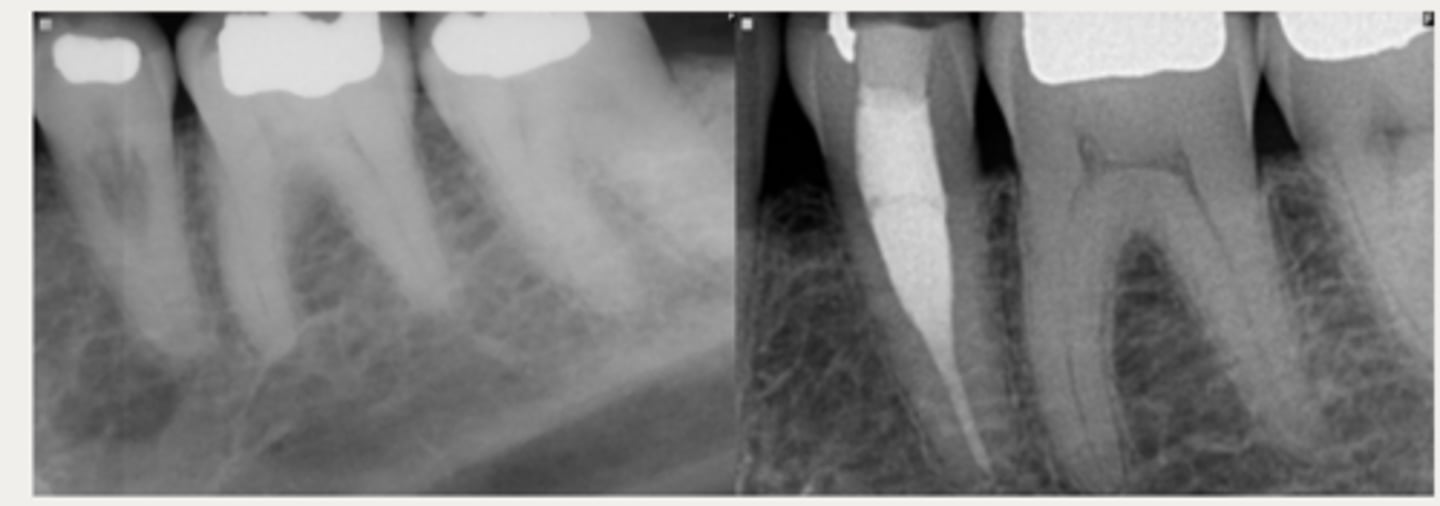

External cervical resorption (Invasive Cervical Resorption)

ID the type of resorption:

- Usually an incidental radiographic finding, especially for less advanced lesions

- Variable appearances; may be a well-defined or irregular radiolucency around the cervical aspect of the tooth

- A portal of entry is always present in the cervical region of the tooth

- The chamber/canal outline is often visible as the innermost layer of predentin around the chamber is not resorbed

Patient presents with these radiographic findings, what type of resorption?

- Incidental finding

- Radiolucency around cervical aspect of tooth

- Portal of entry present in cervical region

- Chamber/canal outline is visible

CBCT

What is the gold standard for diagnosis and treatment planning of External Cervical Resorption (ECR) lesions?